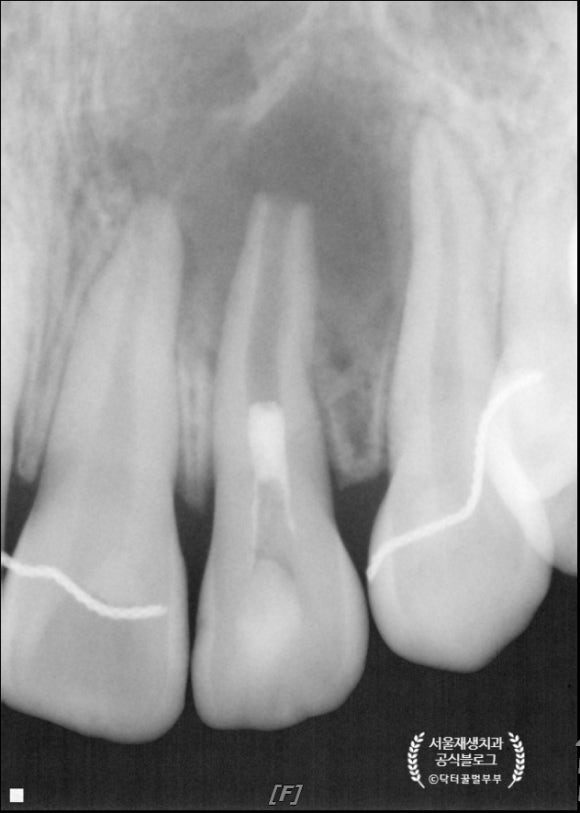

세 달 후에 왔습니다.

병소가 확연히 줄어든 것이 보입니다.

뿌리도 조금 더 두꺼워졌군요.